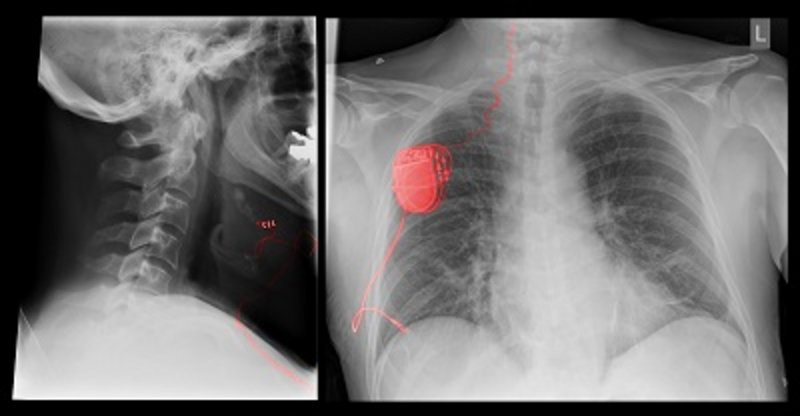

„Bei Herrn Schuberth wurde im Rahmen einer Untersuchung im Schlaflabor eine schwergradige obstruktive Schlafapnoe diagnostiziert. Das Tragen einer nächtlichen Atemmaske ist in einem solchen Fall die Standardtherapie. Dabei werden die Atemwege mittels Überdruck offengehalten. Doch die Maske hat den Schlaf von Herrn Schuberth erheblich gestört. Für ihn kam aus diesem Grund nur eine Operation in Frage“, erinnert sich Dr. Fischer. Klaus Schuberth hatte die Wahl zwischen einer aufwändigen Kiefer-OP, bei der der Kieferknochen durchtrennt und nach vorn verlagert wird, und der Implantation eines sogenannten Zungenschrittmachers. Er entschied sich für letzteres. „Der Zungenschrittmacher besteht aus mehreren Einzelkomponenten. Der Pulsgenerator, der unterhalb des Schlüsselbeins eingebracht wird, gibt über eine Stimulationselektrode einen Impuls an den Zungennerv ab. Ein Drucksensor misst die Atmung im Schlaf und übermittelt dem Pulsgenerator den Zeitpunkt der Einatmung. In diesem Moment löst die Elektrode am Zungennerv ein schonendes Zusammenziehen der Zungenmuskulatur aus“, berichtet PD Dr. Vielsmeier. Dank dieses neuen High-Tech-Behandlungsverfahrens bleiben die Atemwege nachts frei und der Schlaf ist ungestört. „Der erste Patient, den wir vor wenigen Monaten mit dieser Technologie versorgt hatten, kann nun endlich wieder seiner Arbeit als Berufskraftfahrer nachgehen. Er hatte vor der Therapie im Schlaf rund 45 Atemaussetzer pro Stunde. Das erhöht die Gefahr des Sekundenschlafes am Steuer deutlich und geht mit einem hohen Unfallrisiko einher. Seine nächtlichen Wachphasen liegen nun im unbedenklichen, normalen Bereich und der Patient ist sehr zufrieden“, freut sich Dr. Fischer über den Erfolg mit der noch jungen Technologie.